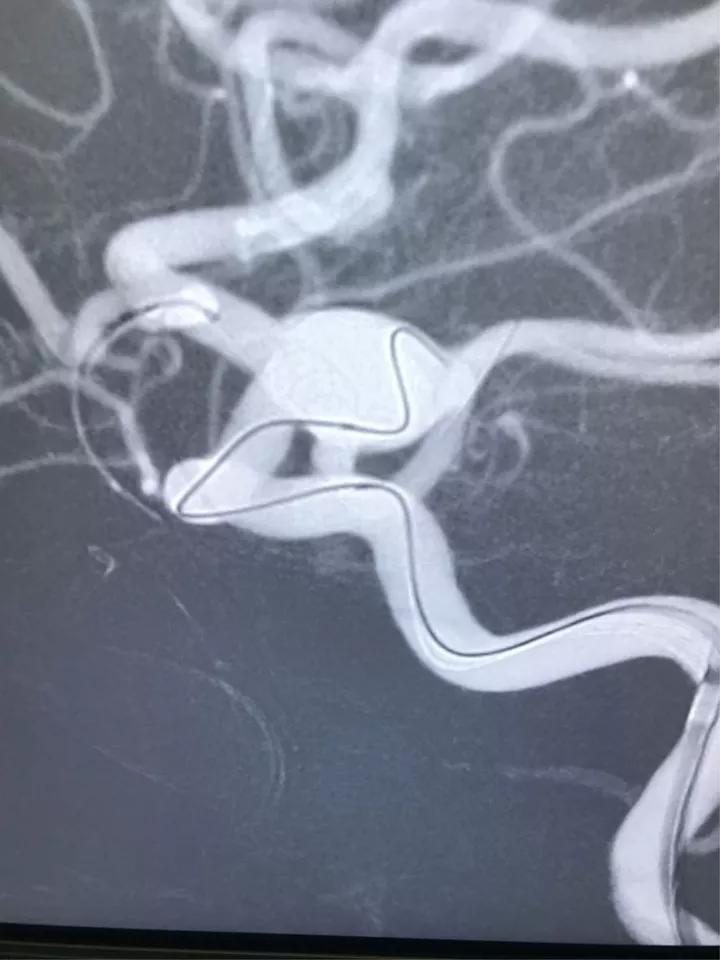

男,49岁,蛛网膜下腔出血

左侧后交通动脉瘤,胚胎型大脑后动脉

3D

局部观,宽颈,涉及颈内动脉和后交通动脉

椎动脉造影见左侧大脑后动脉P1段很细

栓塞的关键是既要保持颈内动脉通畅,又要保持后交通动脉通畅。双导管单纯填塞;通过颈内动脉释放支架灯笼技术辅助是可选的方案。本例是通过后交通动脉释放支架,利用支架摆尾技术(half-T)来进行栓塞。支架导管塑型